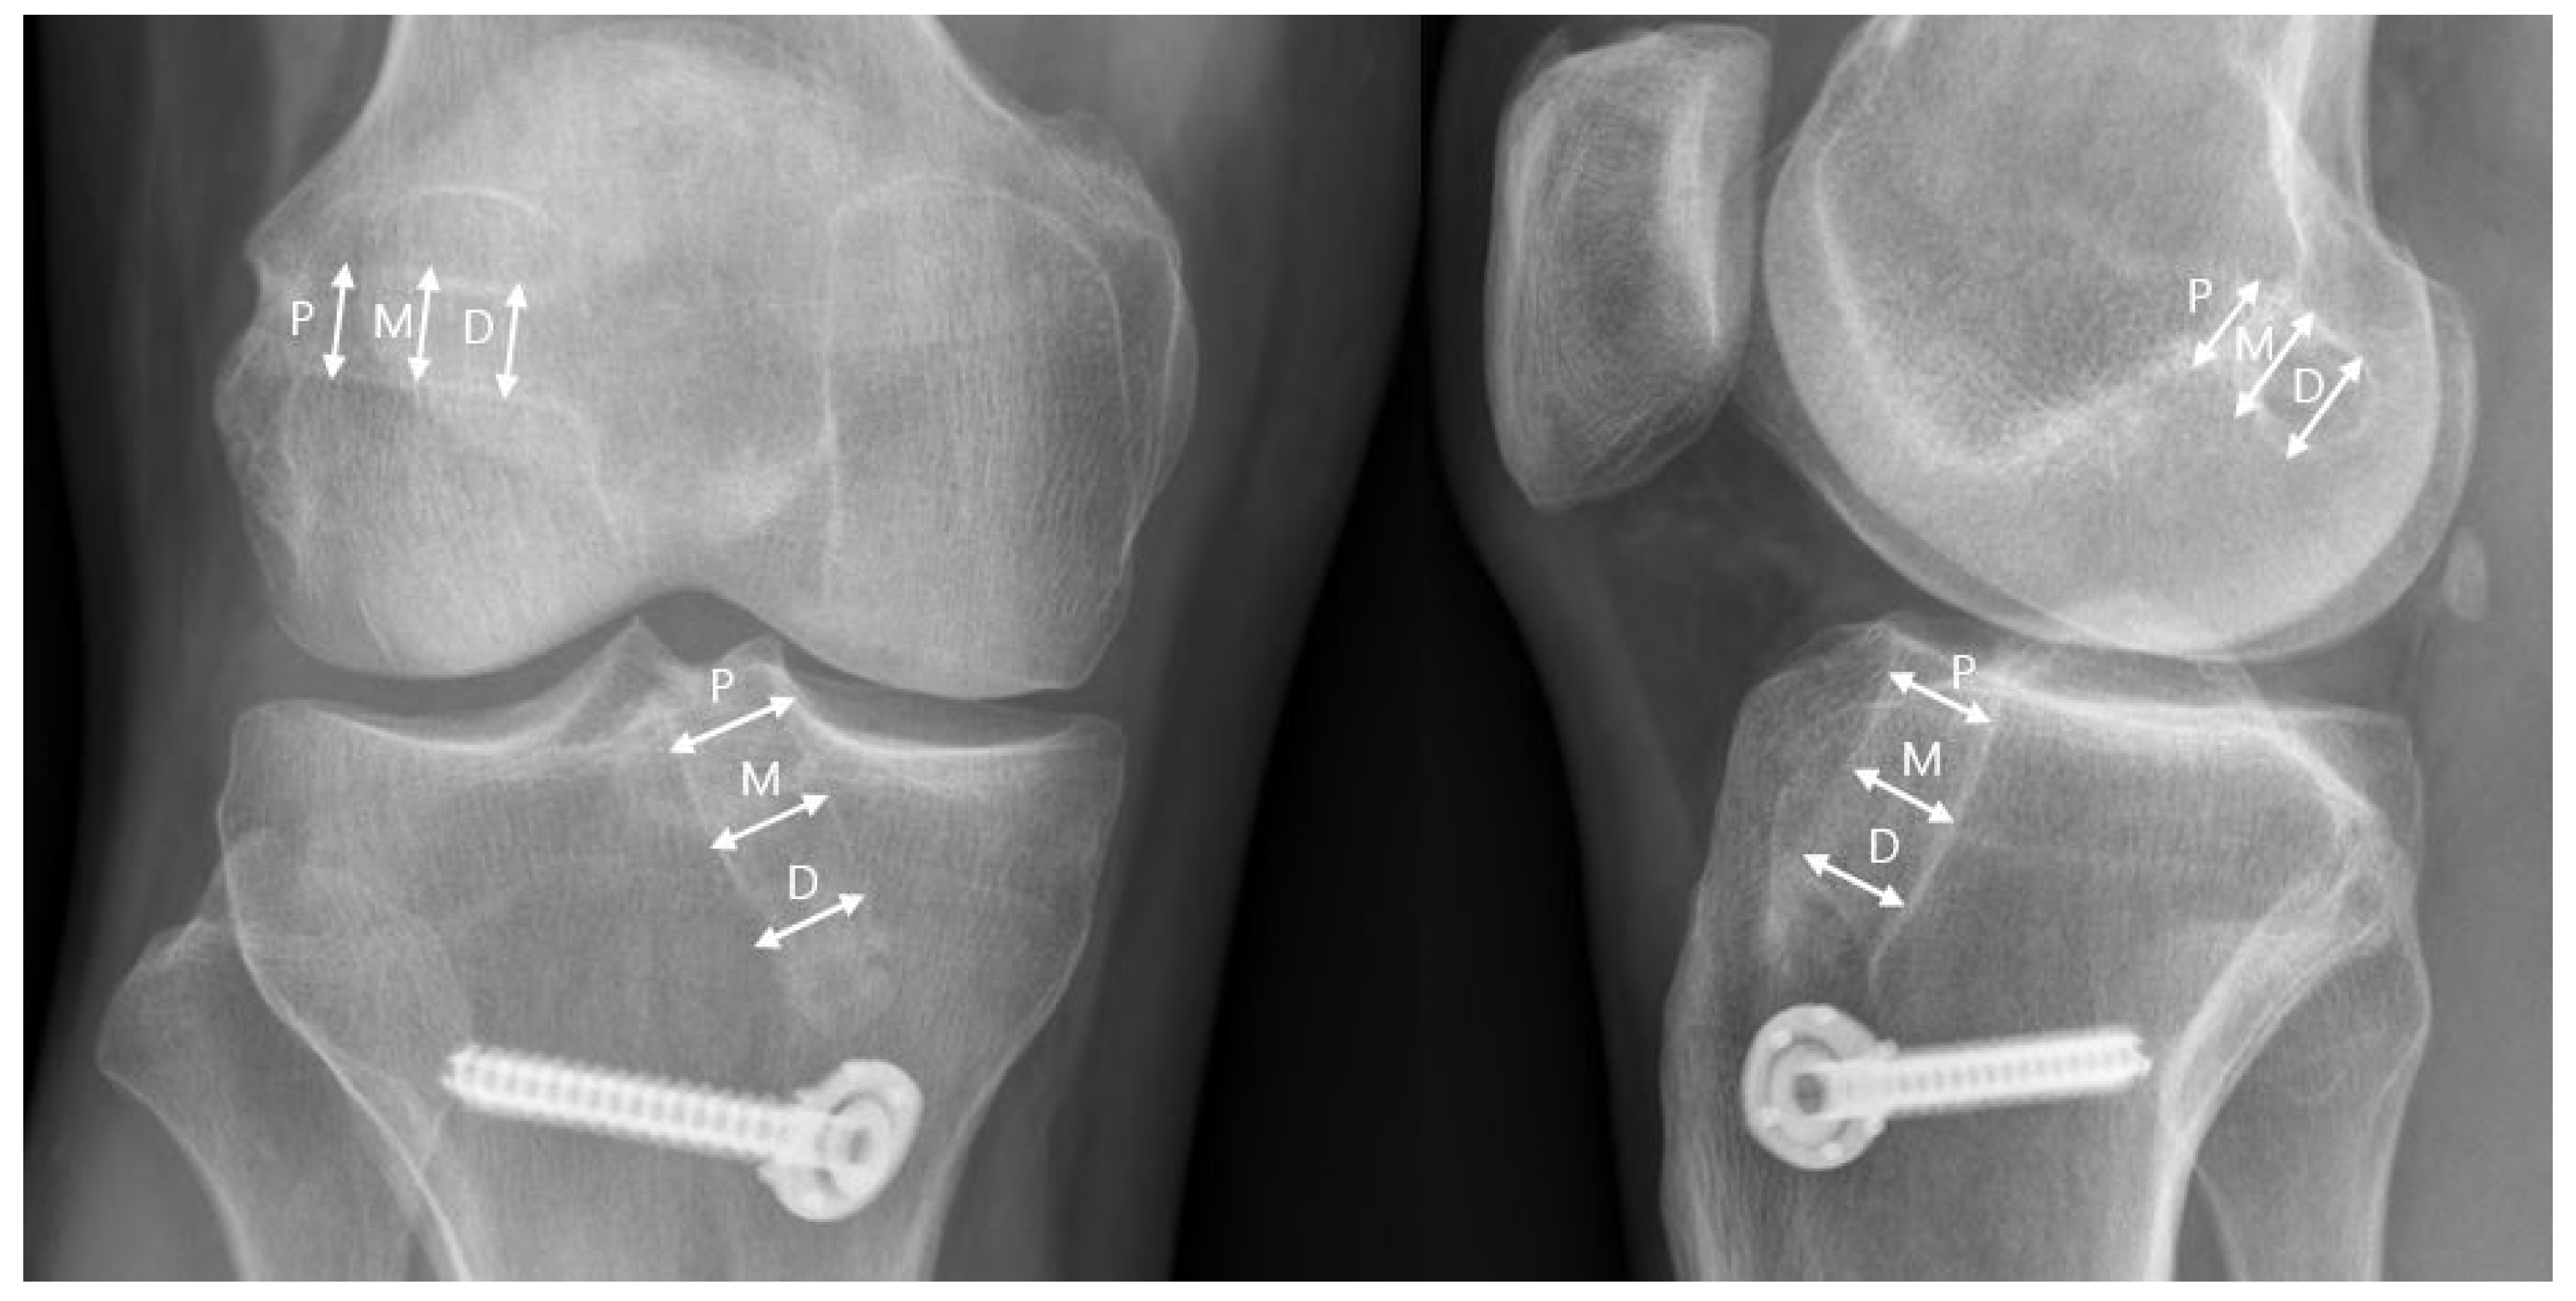

2.3. Radiographic Evaluation